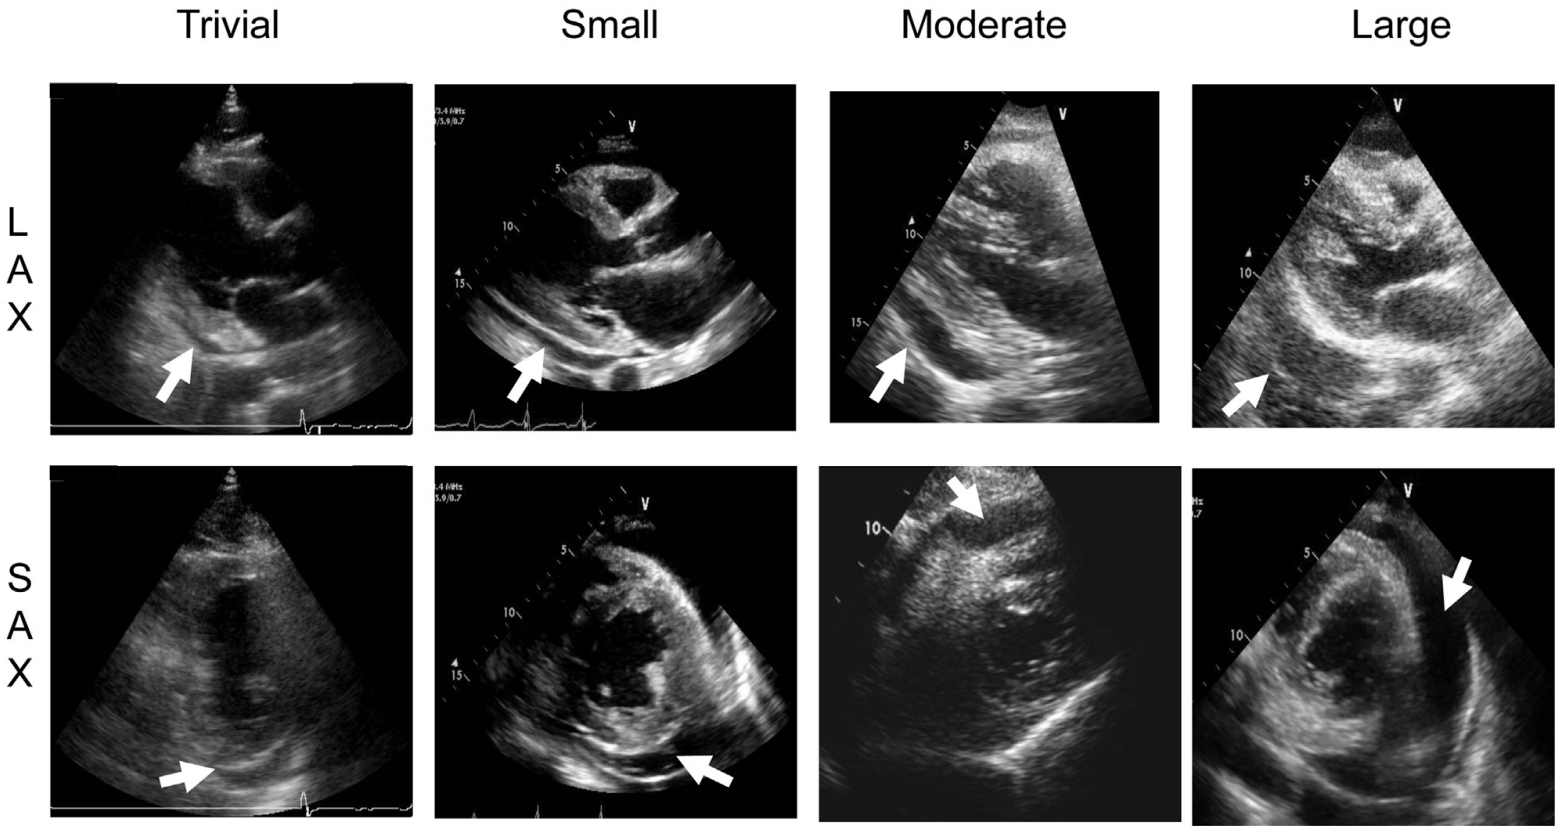

Sizing

• Measure between visceral and parietal pericardium at end diastole (multiple spots to increase accuracy to assess volume)

• Trivial (<10mm) <50mL

• seen only in systole

• Small (<10mm) 50-100mL

• Moderate (10-20mm) 100-500mL

• Large (>20mm) >500mL

Examples

ASE